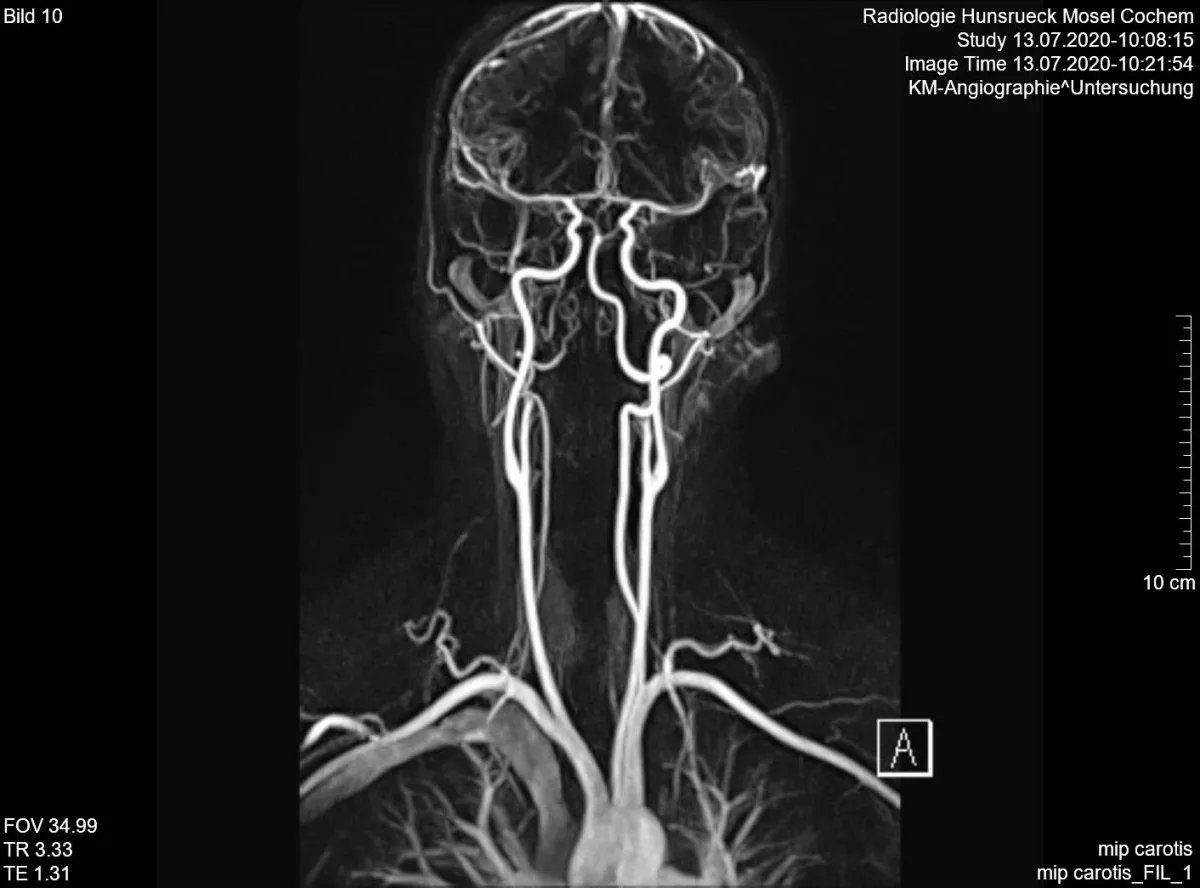

Сегодня трудно представить себе современный госпиталь без магнитно-резонансного томографа (МРТ). Информатор выяснил, как возник этот аппарат и кому мы обязаны высоким уровнем медицины. Оказывается, космической эре с её изобретениями.

Разработчики технологии МРТ получили Нобелевскую премию. Оно и неудивительно, ведь благодаря этому аппарату врачи могут исследовать внутренние органы и ткани человека. И все это – без хирургического вмешательства! А при чём здесь космос? Всё просто.

Этот и другие сверхважные для современной медицины устройства появились в массовом производстве благодаря технологиям и разработкам Национального управления по аэронавтике и исследованию космического пространства США — NASA.

МРТ-аппараты дорогие. Но они могли бы стоить ещё больше и быть малодоступными для большинства, если бы не открытие, сделанное в рамках финансируемого NASA проекта по исследованиям в области авиации.

Оказывается, в 2001 году благодаря сотрудничеству между космической отраслью и промышленностью, открытый учеными полупроводник удалось внедрить в массовое производство. Впоследствии его начали применять во множестве различных сфер, в частности, в производстве МРТ-аппаратов, что позволило значительно удешевить их.